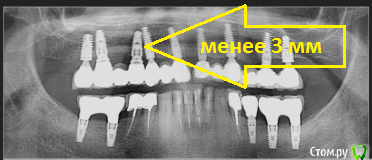

___49___ Опубликовано 25 апреля, 2019 Поделиться Опубликовано 25 апреля, 2019 Спасибо Петр . Какой у Вас прогноз относительно близко расположенных друг к другу имплантов 17\16 и 14\13 ? Ссылка на комментарий

Дмитрий Л. Опубликовано 25 апреля, 2019 Поделиться Опубликовано 25 апреля, 2019 Спасибо Петр . Какой у Вас прогноз относительно близко расположенных друг к другу имплантов 17\16 и 14\13 ?Это оптг, оценивайте по фото) Ссылка на комментарий

___49___ Опубликовано 27 апреля, 2019 Поделиться Опубликовано 27 апреля, 2019 У меня хороший долгосрочный, А у Вас? Это оптг, оценивайте по фото) Рад был бы ошибаться , объективно можно узнать лишь по КТ, оценить по фото к сожалению тоже не могу , так как импланты в разных векторах . Петр не сочтите за занудство , мне до Вас очень далеко, еще раз спасибо что делитесь подобными кейсами . Ссылка на комментарий

pit Опубликовано 28 апреля, 2019 Автор Поделиться Опубликовано 28 апреля, 2019 Рад был бы ошибаться , объективно можно узнать лишь по КТ, оценить по фото к сожалению тоже не могу , так как импланты в разных векторах . Петр не сочтите за занудство , мне до Вас очень далеко, еще раз спасибо что делитесь подобными кейсами . Если бы импланты стояли слишком близко друг к другу, то на этапе установки ФД была бы потеря кости. в апикальной части это не имеет значения Ссылка на комментарий